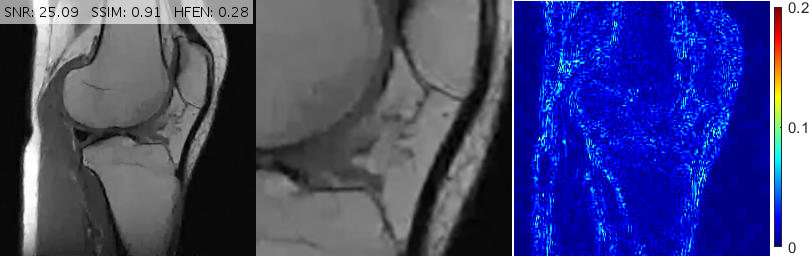

Fig. 11 shows reconstructions for an FSE sagittal knee slice under 16% radial sampling. Solutions provided by TGV+Sh, pFISTA, GBRWT, DAMP and BM3D give rise to incoherent, streaking and block artifacts observable in the magnified views. Deep ADMM Net, TL and FDLCP provide more acceptable results, however, the proposed method gives the best and sharpest reconstruction.

For convenience, in Figs. 10, 11 and 13 we have inserted the SNR, SSIM and HFEN values for each method to the top of the corresponding reconstructed image. Moreover, some reconstruction errors in compared methods and their corrections in the proposed method are annotated with arrows.